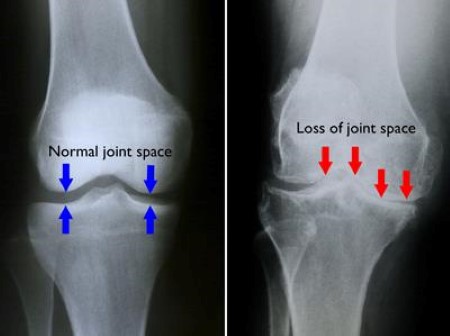

Knee arthritis is known to affect joint functionality causing knee pain and even leading to disability as it progresses. As the cartilage disintegrates, it can cause pain, stiffness, and swelling. The loss of cartilage, the wearing of the bones, and the bony spurs can change the shape of the joint.

As time goes on, the bones will start to rub together, and bone spurs can develop. Stage 2 (mild) stage 3 (moderate) stage 4 (severe) takeaway. Bilateral knee arthritis occurs when both knees are affected with oa.

Learn about the causes, symptoms and treatment. There are different stages of knee osteoarthritis (oa), with 0 assigned to a normal, healthy knee right up to the advanced stage 4, that is severe oa. With oa, the cartilage within a joint begins to break down and the underlying bone begins to change.